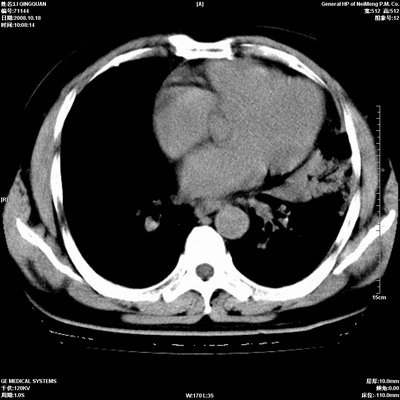

以下是引用duguo在2008-10-19 13:59:00的发言:[br]左肺上叶支气管狭窄,首先考虑中心型肺癌伴阻塞性肺炎\\肺不张.

以下是引用ybing在2008-10-19 12:58:00的发言:[br]左肺上叶阻塞性炎症-建议支气管镜进一步检查除外中央型肺癌

以下是引用随光逐影在2008-10-19 14:31:00的发言:[br]考虑左肺中央型肺癌并左肺上叶阻塞性肺炎,肺不张。